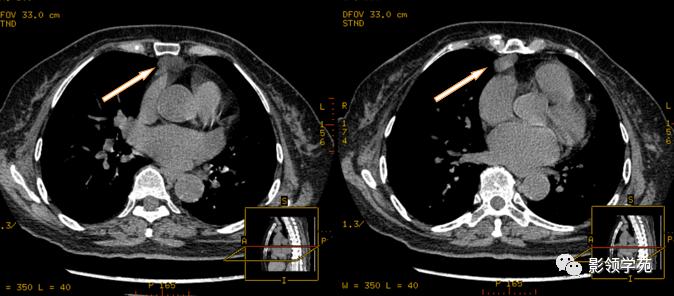

淋巴结肿大融合,压迫上腔静脉,致上腔静脉狭窄

淋巴结肿大融合,轻度强化,与血管形成鲜明对比

融合呈团的淋巴结中央见片状坏死